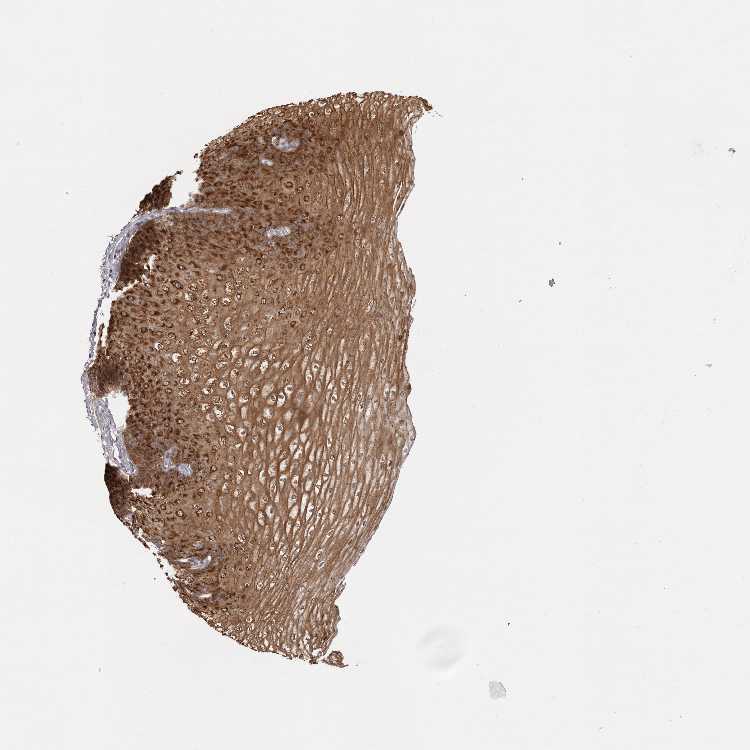

ESOPHAGUS - Antibody stainingi

Antibody staining in the annotated cell types in the current human tissue is reported as not detected, low, medium, or high, based on conventional immunohistochemistry profiling in selected tissues. This score is based on the combination of the staining intensity and fraction of stained cells.

Each image is clickable and will lead to virtual microscopy that enables deeper exploration of all samples and also displays staining intensity scores, fraction scores and subcellular localization as well as patient and tissue information for each sample.

Antibody HPA028581

Squamous epithelial cells High